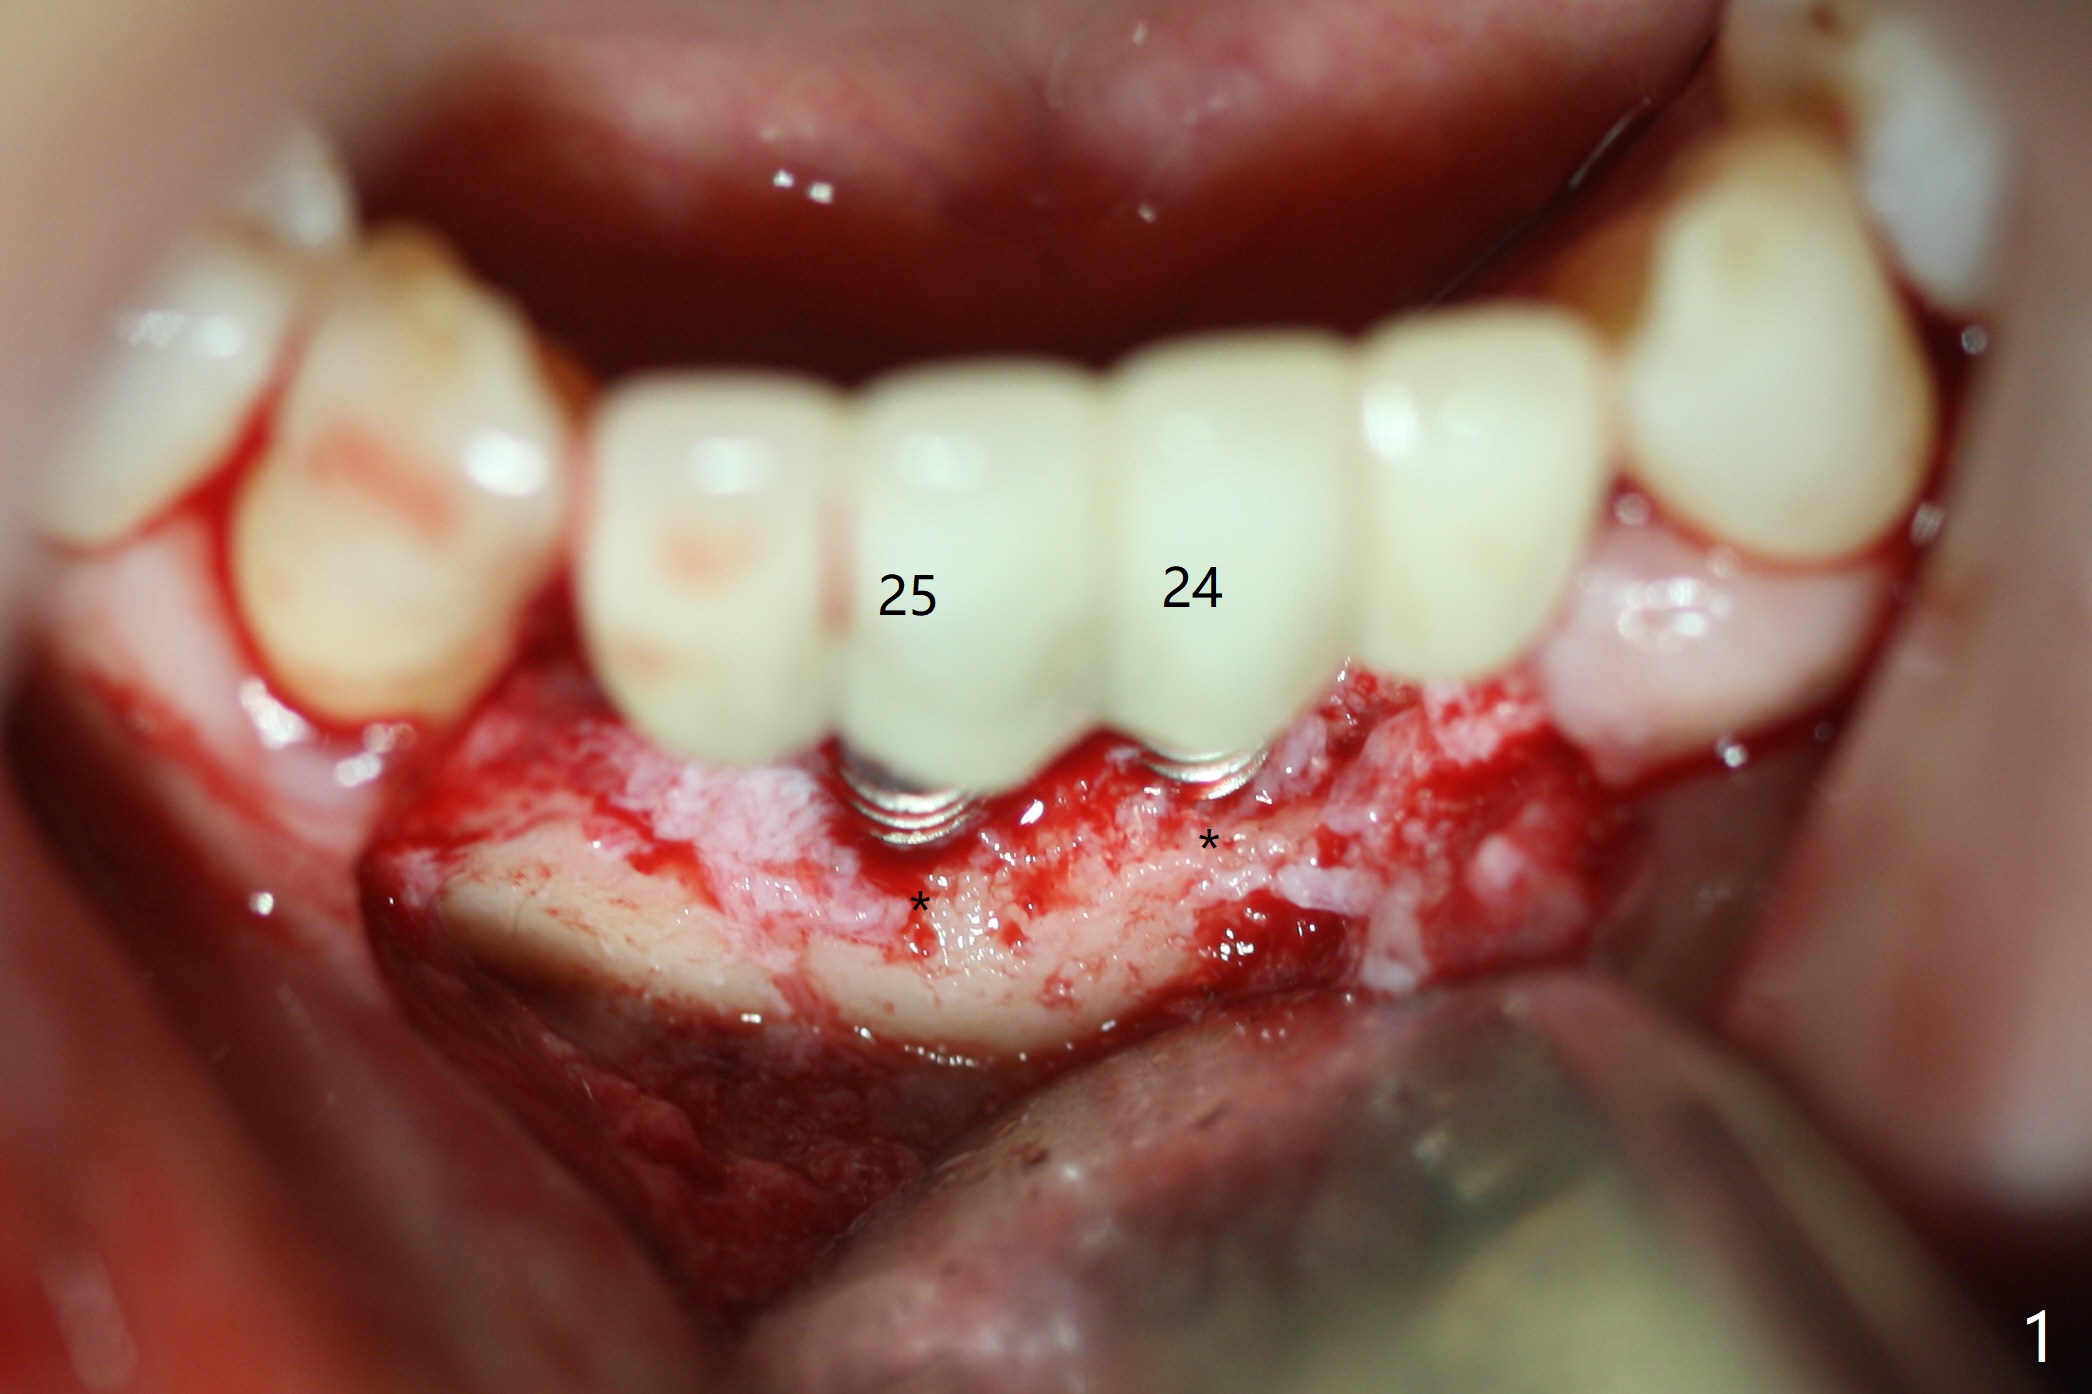

The fenetration found buccal to #25 two months post cementation persists, although asymptomatic, 4 months post cementation. Blood is drawn for PRF. In fact the implants at #24 and 25 are exposed buccal; there is limited amount of the buccal bone (Fig.1 *). After granulation tissue removal, Titanium brush is used to clean the implant threads. Allograft and Osteogen are mixed with PRF liquid to form gel, which is placed over the exposed implant threads. The bone graft is covered with a piece of PRF membrane and a piece of collagen membrane (Fig.2 C). Immediately postop PA (Fig.3) and CBCT (Fig.4) show that the implants have sufficient clearance between them. The implant thread exposure is most likely due to failure to place the implants deep enough and the implants are slightly large relative to the ridge (Fig.5-8). If the bone graft does not heal, new type of 1-piece implants (Fig.9,10 (green) smaller in diameter, 2 or 2.5 mm ) with longer abutment (pink) will be placed subcrestal buccal with guide.